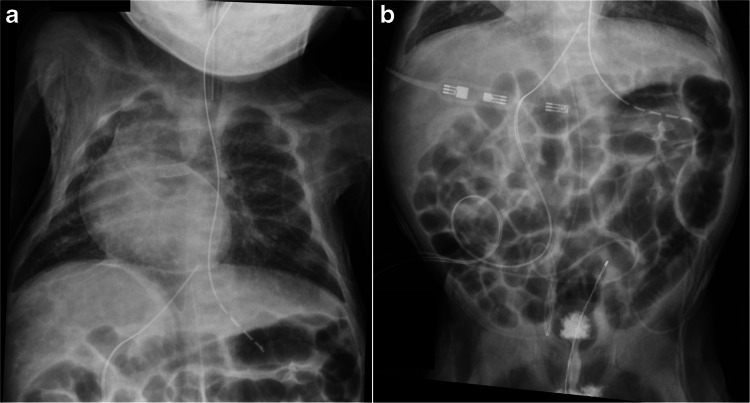

背景:弥漫性浆膜和软组织增强是婴儿心导管置入术后罕见的影像学现象。浆膜和软组织增强的外观可以模拟气腹,可能导致误诊和不必要的诊断程序。虽然病例报告中记录了浆膜和软组织增强,但没有研究系统地评估与其发展相关的危险因素。目的:确定婴儿心导管术后浆膜及软组织强化的频率,并确定与此现象相关的临床及影像学因素。材料和方法:本回顾性研究分析了2010年1月至2019年9月期间在我院接受心导管插入术的婴儿。手术后2天内获得的腹部x线片由三名儿科放射科医生独立审查是否存在浆膜和软组织增强。从电子病历中提取临床数据,包括对比剂、肾功能和心脏生理学。统计分析包括t检验和逻辑回归,以确定与浆膜和软组织增强相关的因素,并使用Fleiss kappa检验评估观察者间的信度。结果:在1796名接受心导管插入术的婴儿中,294名接受了腹部x线片随访。在21例(7.1%)患者中,所有三名放射科医生均发现浆膜和软组织增强。与浆膜和软组织增强相关的重要因素包括插管前和插管后肌酐水平较低(术前0.36±0.17 vs 0.46±0.30 mg/dL;P = 0.043;后0.35±0.11 vs 0.45±0.29 mg/dL;P=0.009),对比度更高(31.8±21.4 vs 21.0±18.1 mL;P=0.013),单位体表面积造影剂体积更高(123.0±69.2 vs 80.8±56.2 mL/m^2;P = 0.002)。浆膜和软组织增强在双心室心脏生理患者中更常见(125/294;42.5%比169/294;57.5%)。结论:一小部分新生儿心导管术后出现浆膜和软组织增强,并与较高的造影剂剂量和体表面积调整的造影剂体积有关。儿科放射科医师对浆膜和软组织增强的认识有助于避免气腹的误诊。

Background: Diffuse serosal and soft tissue enhancement is a rare imaging phenomenon observed in infants following cardiac catheterization. The appearance of serosal and soft tissue enhancement can mimic pneumoperitoneum, potentially leading to misdiagnosis and unnecessary diagnostic procedures. While serosal and soft tissue enhancement has been documented in case reports, no studies have systematically evaluated the risk factors associated with its development.

Objective: To determine the frequency of serosal and soft tissue enhancement in infants following cardiac catheterization and identify clinical and imaging factors associated with this phenomenon.

Results: Among 1,796 infants who underwent cardiac catheterization, 294 had follow-up abdominal radiographs. Serosal and soft tissue enhancement was identified as present by all three radiologists in 21 patients (7.1%). Significant factors associated with serosal and soft tissue enhancement included lower pre- and post-catheterization creatinine levels (pre- 0.36 ± 0.17 vs 0.46 ± 0.30 mg/dL; P=0.043; post- 0.35 ± 0.11 vs 0.45 ± 0.29 mg/dL; P=0.009), higher contrast volume (31.8 ± 21.4 vs 21.0 ± 18.1 mL; P=0.013), and higher contrast volume per body surface area (123.0 ± 69.2 vs 80.8 ± 56.2 mL/m^2; P=0.002). Serosal and soft tissue enhancement occurred more frequently in patients with bi-ventricular cardiac physiology (125/294; 42.5% compared to 169/294; 57.5%).

Conclusion: Serosal and soft tissue enhancement occurs in a small proportion of neonates following cardiac catheterization and is associated with higher contrast dosages and body surface area-adjusted contrast volumes. Awareness of serosal and soft tissue enhancement among pediatric radiologists is helpful to avoid misdiagnosis of pneumoperitoneum.